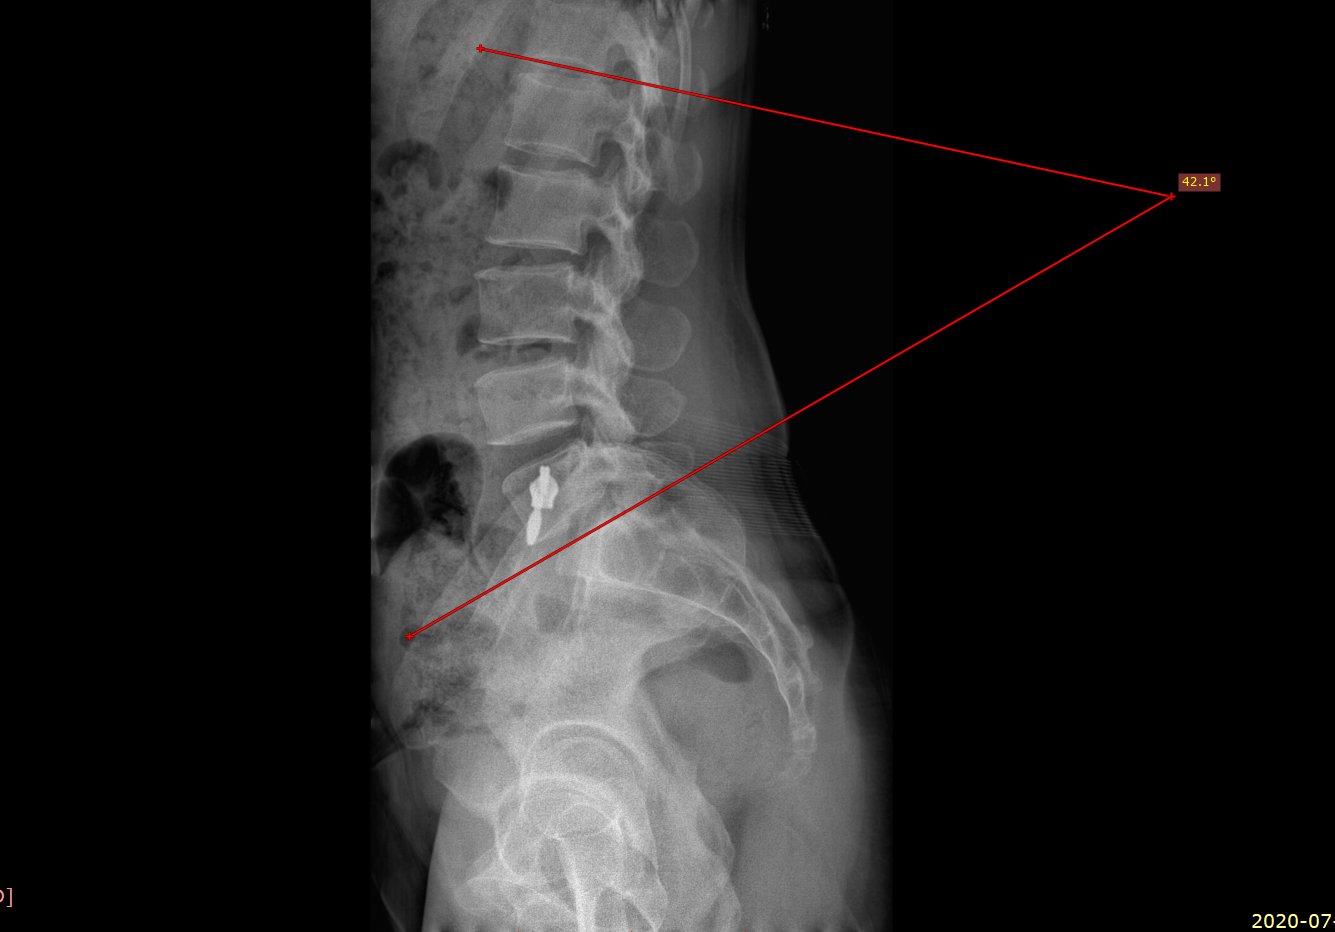

골반 전방 경사 되면, 요추는 과전만 된다고....

그리고, 군의관으로 사단 의무대 근무 당시 정말 열심히 엑스레이 찍어서 확인해 봤는데...

왠 걸, 안 맞더라구요....

사람 몸이 제각각이고 좌우 대칭이 안 된다는 걸, 교과서적으로 맞질 않다는 걸 아주 절실히 봤습니다.

추나 치료나 스트레칭, 도수 치료 등을 시행하시는 분들은 꼭 사진 촬영을 통해서 확인을 해 보세요.

눈으로 보는 것과는 확연히 다릅니다.